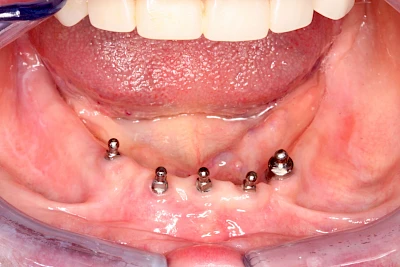

Implantate: Prothesen

Bei herausnehmbaren Prothesen werden Implantate eingesetzt, um den Halt und den Tragekomfort der Prothesen zu verbessern. Dazu kommen verschiedene Verbindungselemente zum Einsatz:

- Teleskope

- Kugelköpfe

- Tellerförmige Lokatoren

- Stege

- Magnete (selten)

Neben rein implantat-getragenen zahnärztlichen Versorgungen werden bei herausnehmbaren Prothesen Implantate auch in Sinne einer "strategischen Pfeilervermehrung" ergänzend zu eigenen Zähnen zur Verankerung eines Zahnersatzes genutzt.

Varianten zur Verankerung von abnehmbarem Zahnersatz auf Implantaten